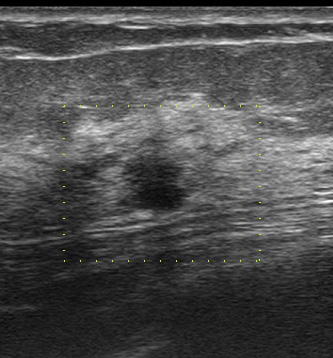

初回の検診エコー(今回送られてきたもの)

縦長! 不整型!

これ(去年に何もなかったのに、しかも60歳代)で要精査に何故しない!!

別角度

やっぱり、どう見ても「癌疑い」

何で、カテゴリー2で要精査としなかったのだろう。

検診機関なので「当然」エコーは技師が行っています。